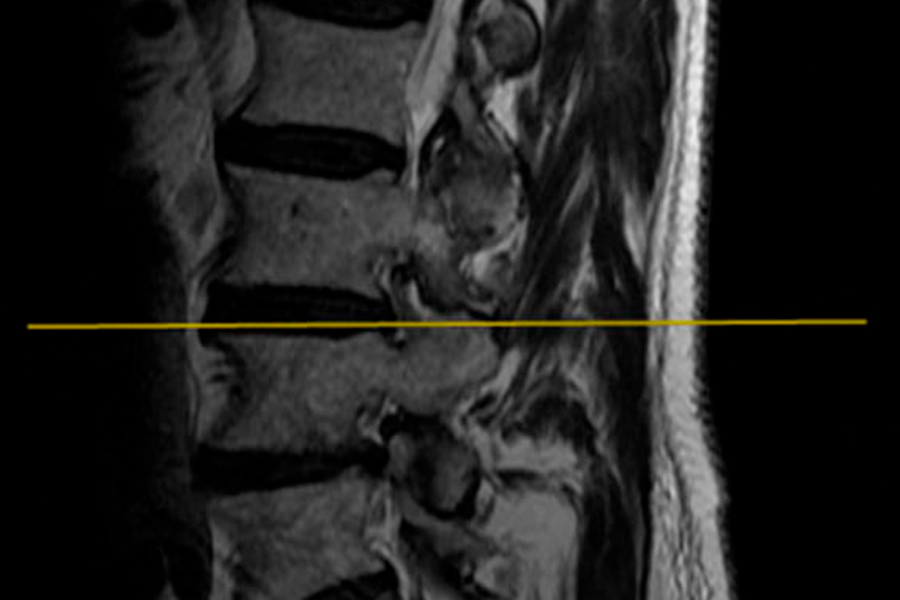

Caso clínico: endoscopia de columna multinivel L4L5 y L5S1

Los síntomas que presentaba el paciente eran dolores acentuados en las piernas, claudicación a la marcha y calambres y hormigueos en las piernas.

Durante la intervención quirúrgica, se abordarán los dos niveles mediante la técnica de endoscopia de columna.